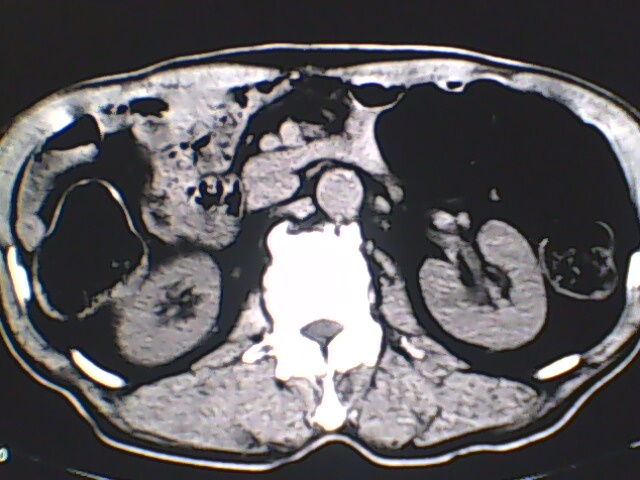

男,56岁,高血压,临床怀疑肾上腺问题,肝脏怎么那么高啊?能描述一下么?

右侧膈膨升,间位结肠,胸腰椎退行性骨关节病,右侧肾上腺可疑增生(图像颗粒太粗,窗太窄,不好看)。

支持 右侧膈膨升,间位结肠;胸腰椎退行性骨关节病;双侧肾上腺可疑增生。